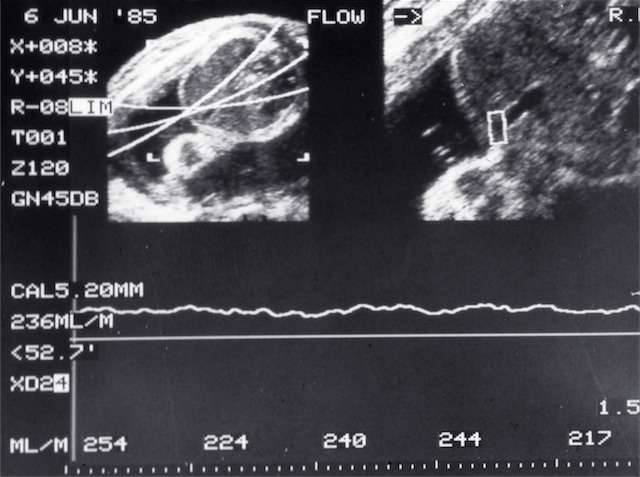

- Umbilical flow measurement (1985)

- Umbilical flow measurement (1986)